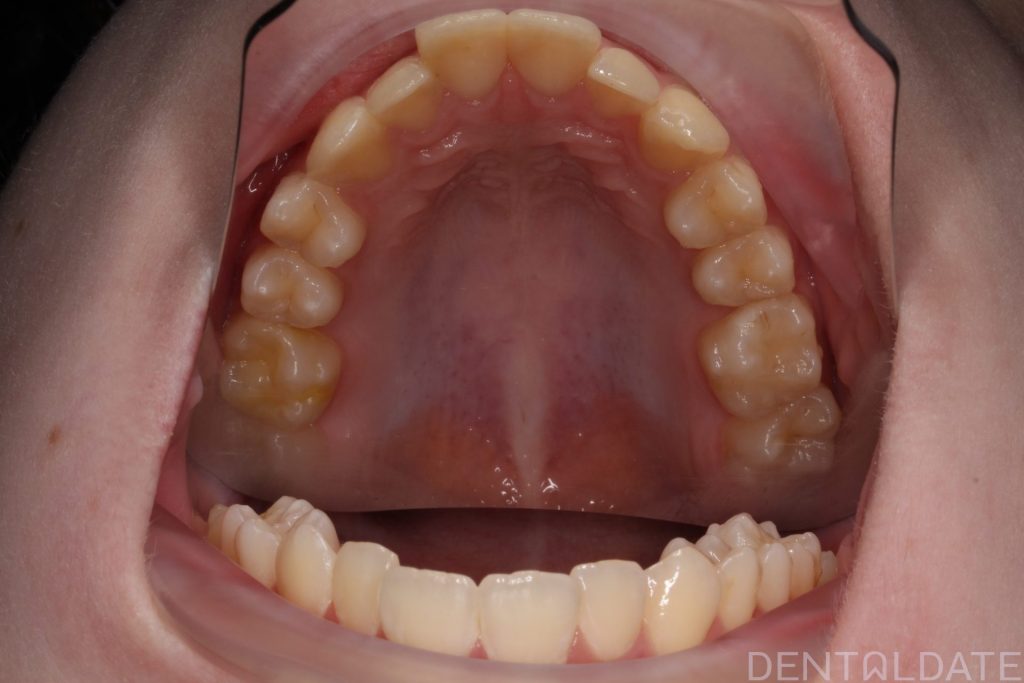

Orthodontic treatment lasted 10 months; currently, the patient is preparing for braces removal.